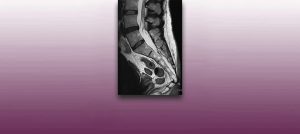

Institut Chiari & Siringomielia & Escoliosis de Barcelona is highly specialized neurosurgical center dedicated to the diagnosis and treatment of spinal and brain disorders, with a focus on the clinical concept of Filum Terminale Disease. Conditions treated include: